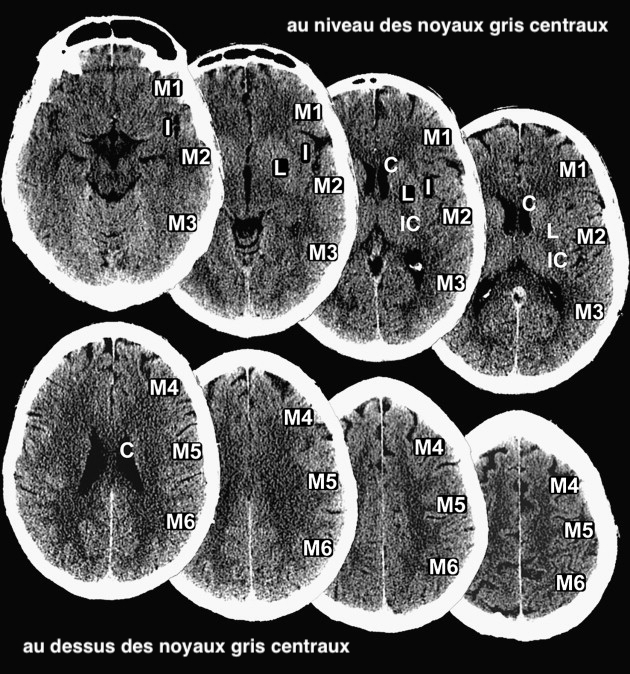

Anatomie vasculaire de l'artère cérébrale moyenne

Anatomie segmentaire :

• M1 : segment sphénoïdal ou horizontal

• origine : terminaison de la carotide interne ;

• trajet : lateralement, parallellement au rebord sphénoïdal ;

• terminaison : à la bifurcation principale M1-M2

• M2 : segment insulaire

• origine : à la bifurcation principale M1-M2 ;

• trajet : direction postérosupérieure dans la fente insulaire ;

• terminaison : dans le sillon circulaire de l'insula (sillon tout autour de l'insula), en faisant une épingle à cheveu ;

• M3 : segment operculaire

• origine dans le sillon circulaire ;

• trajet : lateralement le long de l'opercule frontopariétal ;

• terminaison : surface supérieure/externe de la fissure sylvienne ;

•  M4 : segment cortical

• origine : surface supérieure/externe de la fissure sylvienne ;

• trajet : superieurement sur la convexité latérale ;

• terminaison : cortex.